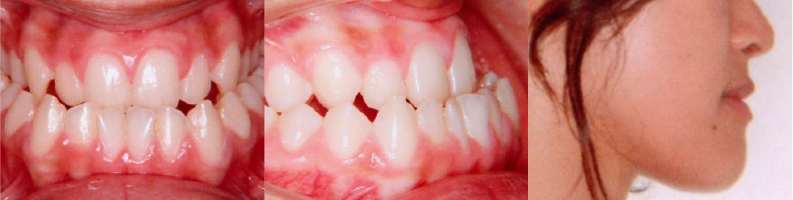

受け口が治って、横顔も綺麗に!

初診時、上下の歯が咬み合っていないことや、口元が出ていることを気にされていました。矯正治療によって、咬み合わせと顔貌が変化したことで、自信を持っていただけたかと思います。同じような受け口で、「こんな咬み合わせ、治るのかな・・・」と不安に思っておられる方は一度ご相談ください。

| 主訴 | 下の歯が出ている、咬んだ時の上の歯と下の歯が咬み合わない、口元が出ている |

| 診断名 | 反対咬合 |

| 年齢 | 22歳9ヶ月 |

上下リンガルブラケット矯正装置 |

| 抜歯部位 | 非抜歯 |

4年1ヶ月(通院回数 49回) |

| 治療費用 | 1,344,000円(当時の総額) |